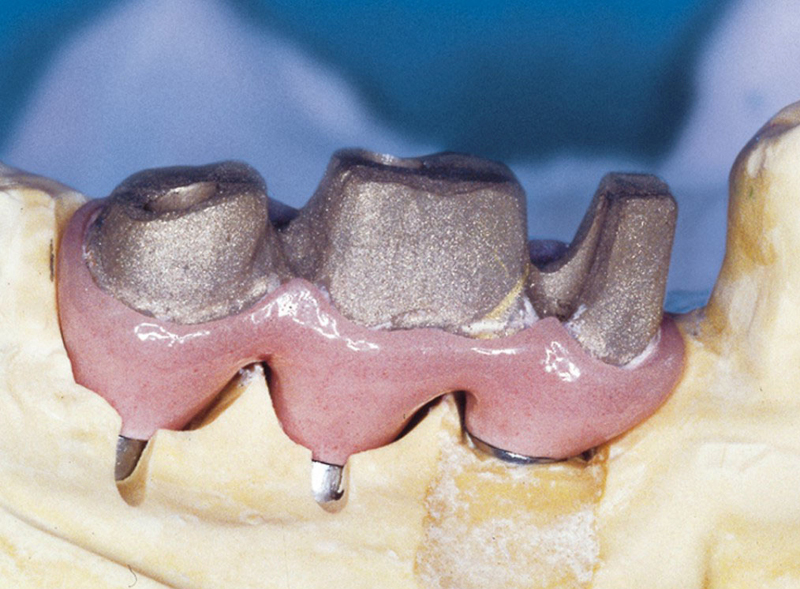

Protetické řešení může být pomocí můstku, který je kotvený na implantátech nebo pomocí jednotlivých korunek na implantátech.

V zásadě je možné do těchto můstků zařadit i přirozené zuby, zejména pokud je potřeba tyto zuby ošetřit proteticky - korunkami. Korunky nebo můstky mohou být na implantáty nacementovány nebo přišroubovány.